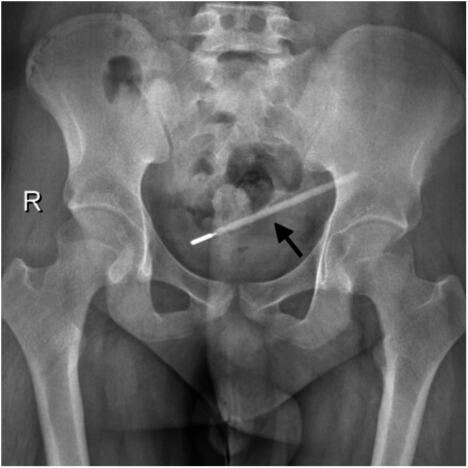

Rutinska poseta bolnici zbog bolova u stomaku pretvorila se u neverovatno otkriće za tridesetdvogodišnjeg muškarca iz kineskog grada Vendžoua. Pacijent, prezimena Vang, javio se u na odeljenje bolnice Medicinskog fakulteta Vendžou, žaleći se na jake bolove. Lekari su ga odmah poslali na dijagnostiku, a snimci su otkrili nešto potpuno neočekivano - u njegovom dvanaestopalačnom crevu, početnom delu tankog creva, nalazio se dugačak i oštar strani predmet. Sumnje su se ubrzo potvrdile: bio je to stari živin toplomer, prenosi PubMed Central.

Stanje je bilo alarmantno. Lekarski rim je utvrdio da vrh toplomera direktno pritiska zid creva stvarajući visoki rizik od perforacije i teškog unutrašnjeg krvarenja. Svako odlaganje moglo je da bude kobno. Kada su suočili pacijenta s otkrićem, Vang je priznao neverovatnu priču koja stoji iza misterioznog predmeta. Ispričao je kako je slučajno progutao toplomer kad je imao 12 godina. U to vreme, rekao je, previše se bojao roditeljske reakcije da bi im priznao šta se dogodilo.

Iako je sama operacija uklanjanja trajala svega dvadeset minuta, bila je izuzetno zahtevna i osetljiva. Toplomer se nalazio u neposrednoj blizini žučnih kanala, što je predstavljalo značajan rizik od oštećenja crevnog zida tokom postupka. Hirurzi su morali da postupaju s krajnjim oprezom, ali zahvat je uspešno završen. Na opšte iznenađenje, toplomer je izvađen potpuno netaknut, premda su oznake za merenje temperature na staklu s vremenom potpuno izbledele.

toplomer

Toplomer koji su izvadili pacijentu iz stomaka nakon 20 godina Foto: PubMed Central